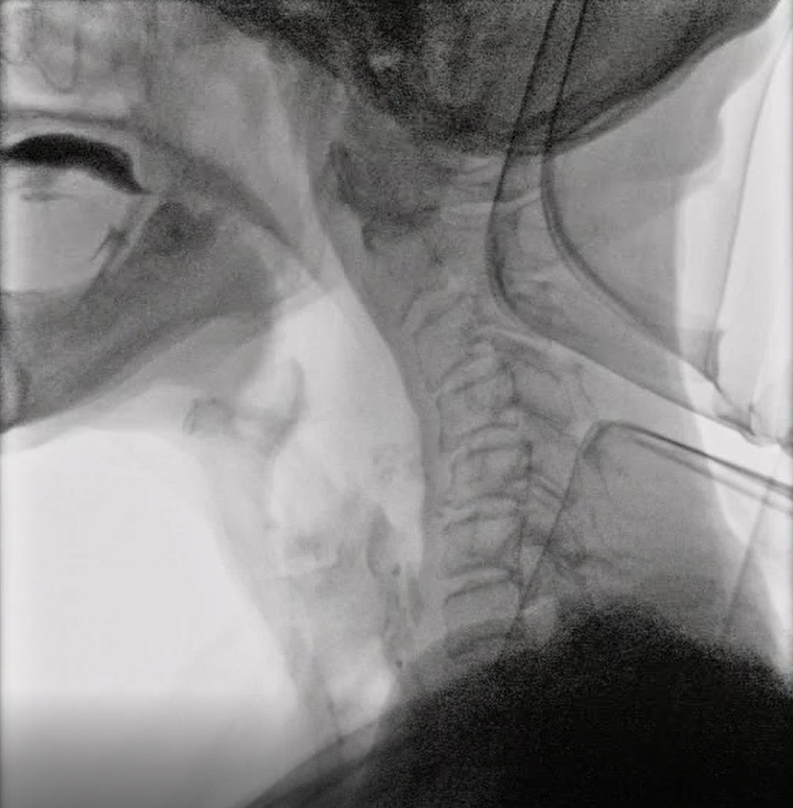

②入院・VF検査(飲み込みのレントゲン検査)

入院初日にVF検査を実施し、嚥下状態を詳しく確認します。